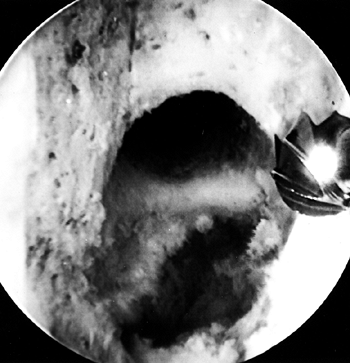

true posterior outlet (Fig. 89.8).

Figure 89.8.

Arthroscopic view of a right knee. The 5.5 mm round burr is just

posterior to a vertical ridge that is two-thirds posterior to the

entrance to the notch. Take this down to fully visualize the

“over-the-top” position. -

When the ridge is identified, place the

burr posterior to the ridge and move it from a posterior to anterior

direction to smooth the ridge. Use a curet to remove soft tissue from

the posterior outlet, and then hook a probe over the posterior edge to

confirm proper “over-the-top” positioning (Fig. 89.9).